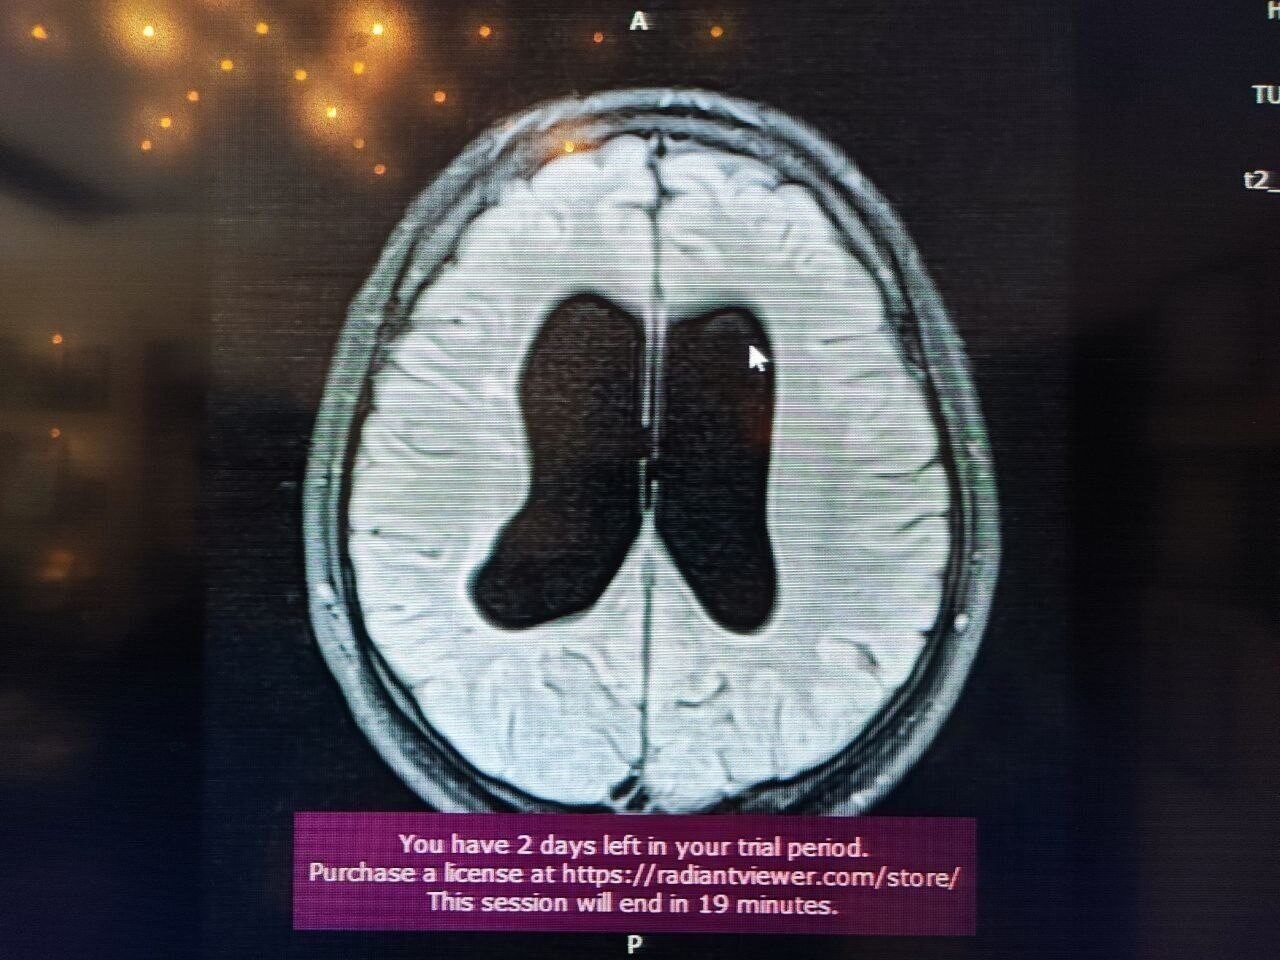

Süreçle ilgili bilgi veren Beyin, Sinir ve Omurilik Cerrahisi Uzmanı Prof. Dr. Orhan Şen, “17 yıl önce, 10 günlük bebekken annesi ve dedesi tarafından bana getirildi. Doğar doğmaz doktorlar ameliyat önermişler. Hidrosefali nedeniyle beyinde su toplanması var, bu nedenle acil ameliyat etmemiz gerekiyor yoksa ölür demişler. Gaziantep ve Adana’da farklı yerlere götürmüşler. Genel olarak hep ameliyat demişler. Ben muayenesini yaptım ve bıngıldak denilen yere baktığımda normal bombelikteydi. Anneye sordum, normal dururken kusma var mı? diye. ‘Hayır, yemek yerken kusma oluyor’ dedi. Muayeneye devam ettiğimde çocuğun klinik tablosu, nörolojik muayenesi ve filmi birbiriyle uyumlu değildi. Bunun üzerine acil ameliyat gerekmiyor, izleyelim. dedim. Bıngıldakta bombe olursa ve arka arkaya kusma olursa o zaman ameliyatını yaparız dedim. Normalde ilk anne karnındayken gelişen süreçte olan bir olay. Radyolojik olarak çocuğun doğar doğmaz bu bulguyu görmemiz, hepsinin aktif hidrosefali olduğu anlamına gelmiyor. Bazen yeni doğanlarda olan ufak kanamalardan kaynaklanabiliyor” dedi.

Sözlerini sürdüren Prof.Dr. Şen “Bizim çocuğumuzda, anne karnında yaşanan bir süreç olduğu için beyine ekstra bir baskı uygulamıyordu. Beyin buna göre gelişmişti. Anne, bizim söylediğimizi tercih etti. O tercihin üzerine şu an 17 yıl geçti. 17 yaşında ve ilkokul ile ortaokulu birinciliklerle tamamlayan genç, şimdi de üniversiteye hazırlanıyor. Bizim burada asıl amacımız, özellikle genç meslektaşlarıma sesleniyorum: Hidrosefali tanısı konulan her çocuk acil ameliyatlık değildir. Bazen arrest hidrosefali olabilir ve şant takmak gerekmiyor. İzlemekte fayda var. Her müdahale cerrahi müdahale değildir. Doğruyu söyleyip göstermek en güzel müdahaledir” diye konuştu.